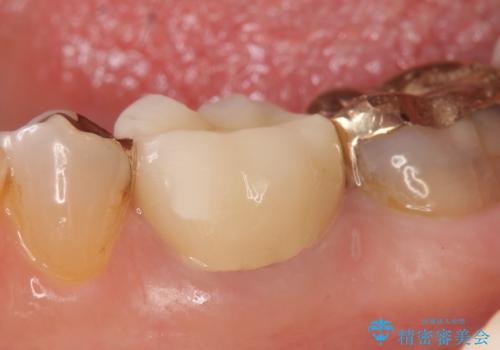

その後症状の消失を確認し、オールセラミッククラウンによる補綴を行いました。

今回用いたオールセラミッククラウンはジルコニアフレームという白い素材の上にセラミックを盛っているため、審美性が非常に高いのが特徴です。

また、ジルコニアは人工ダイヤモンドの材料にも使われているほど高い強度を持っており、そのためオールセラミッククラウンは審美性だけでなく、奥歯やブリッジの補綴も可能とするクラウンです。